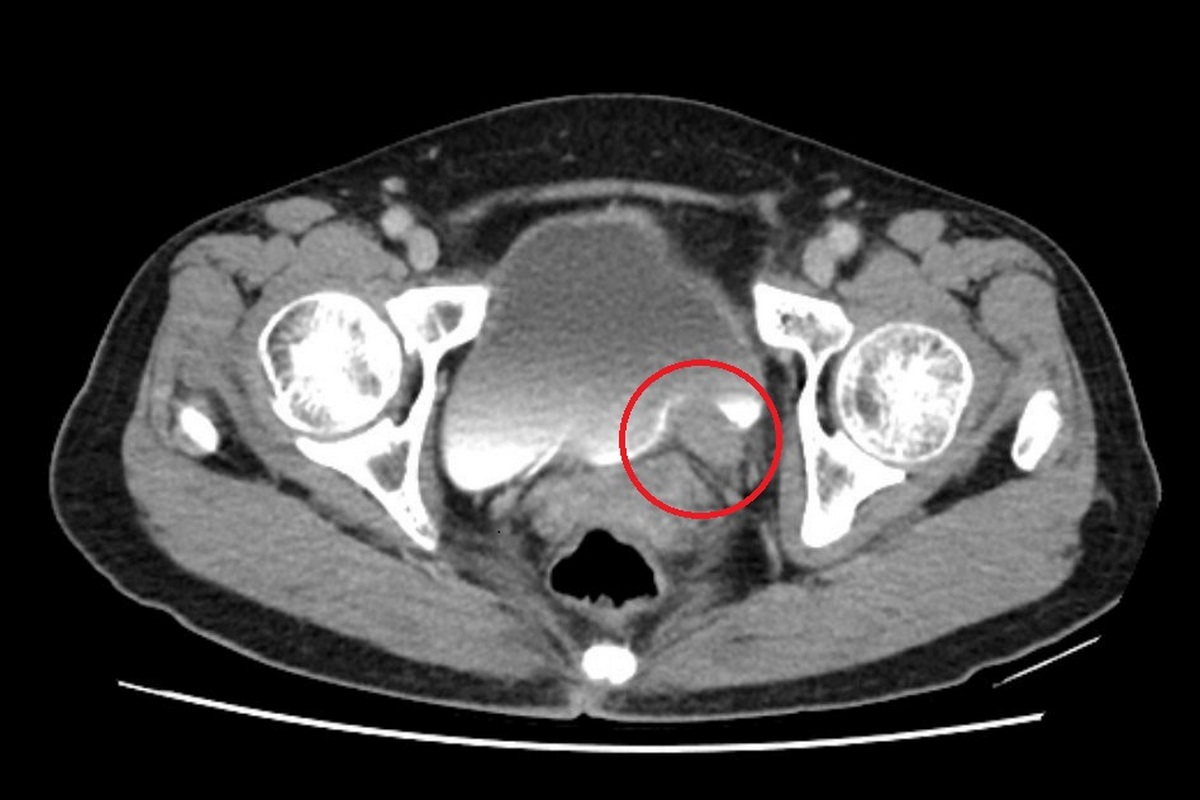

67 歲的林女士一向健康,卻在近期出現間歇性的無痛血尿,她原本以為只是小問題,至台北慈濟醫院檢查後,竟發現左側輸尿管末端長了一顆5公分的腫瘤,並造成腎水腫情形。確診為輸尿管泌尿上皮癌後,許竣凱醫師先安排化療縮小腫瘤,再利用達文西手術切除腫瘤並重建輸尿管,成功保留腎臟功能,林女士術後追蹤至今,病情控制良好。

輸尿管是連接腎臟與膀胱的重要管道,負責將腎臟產生的尿液順利輸送到膀胱儲存與排出。根據衛生福利部統計,泌尿上皮癌發生率每十萬人中約有40-50例,臨床上,醫師會以尿液檢驗、膀胱鏡、超音波與電腦斷層進行診斷,排除泌尿道感染、輸尿管結石等會伴隨疼痛的血尿後,就要高度懷疑腫瘤的可能。許竣凱醫師指出:「長期吸菸、處於環境汙染及具家族史者都是危險因子,輸尿管泌尿上皮癌症狀並不明顯,常見表現為無痛性血尿,若置之不理,腫瘤可能造成阻塞及腎衰竭、或是逐漸擴散,甚至出現遠端轉移,危及生命。」